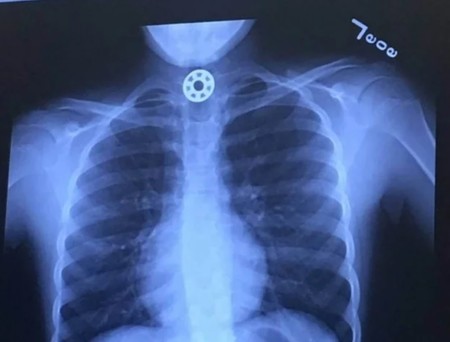

Intentó ayudarla a sacar el objeto fuera con la maniobra de Heimlich. Al ver que no lo lograba fueron al hospital más cercano, donde una radiografía mostró dónde se había quedado atascado el objeto.

Texasspiner

Mediante una endoscopia y bajo sedación pudieron dar con el objeto y extraerlo. Todo acabó bien, pero los padres lo pasaron muy mal por el riesgo de que se moviera y dificultara aún más su respiración.